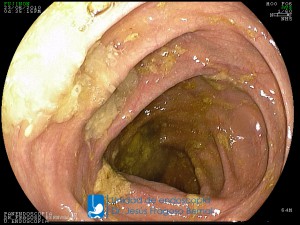

La Unidad de Endoscopía fue creada en 2002 por el Dr. Jesús Fragoso Bernal, es pionera en el estado por la utilización de la tecnología más avanzada, que nos permite ofrecer servicios integrales de diagnóstico y tratamiento para las enfermedades del aparato digestivo.

"La Unidad de Endoscopía se ha caracterizado por un progreso continuo desde su inicio marcando la pauta en los procedimientos endoscópicos en el estado de Tlaxcala y estando siempre a la vanguardia tecnológica."